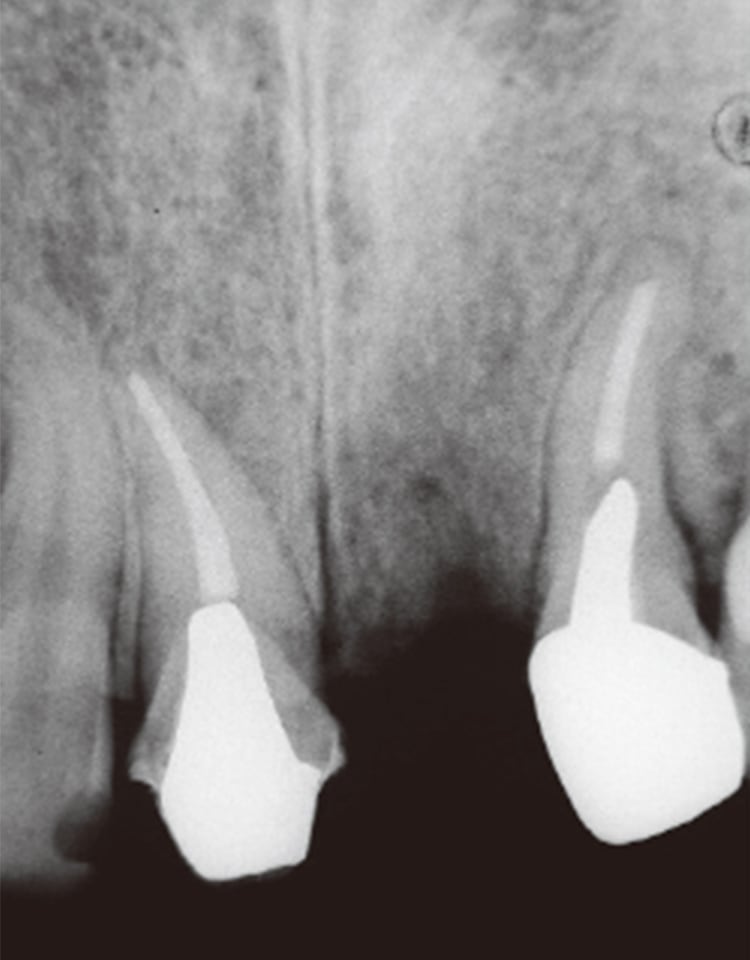

• 初診時上顎前歯部デンタル。1根尖部周囲に骨透過像および歯根破折所見、根近接等が認められる。

図1b 初診時上顎前歯部デンタル。1 根尖部周囲に骨透過像および歯根破折所見、根近接等が認められる。